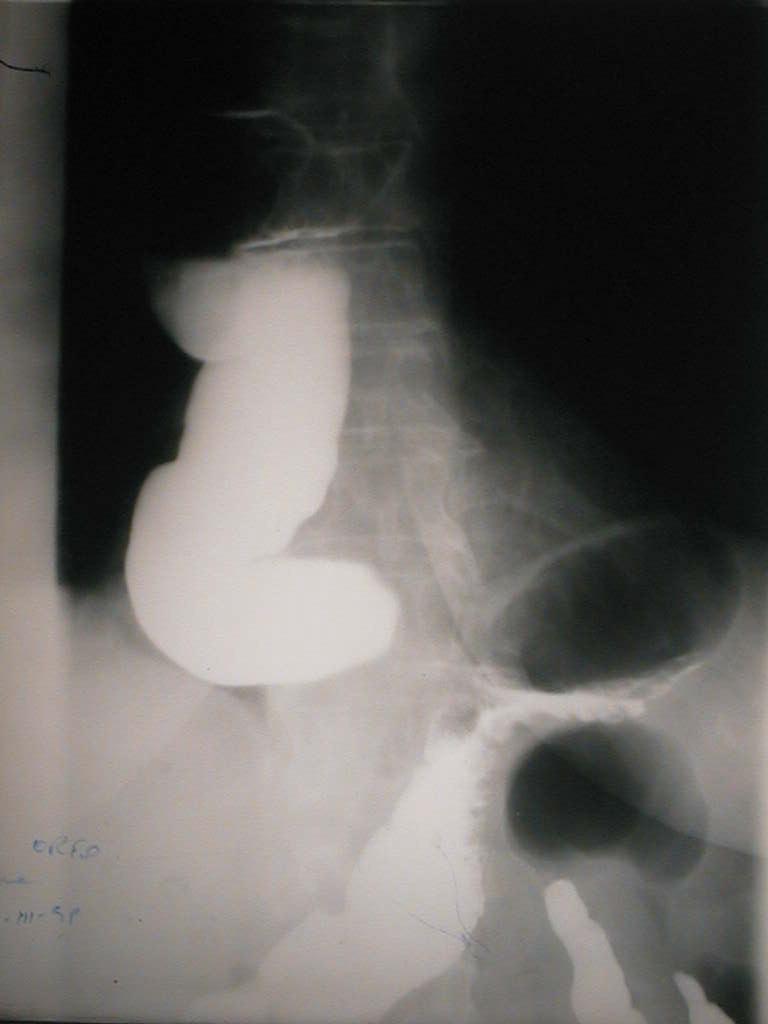

Barium Contrast Radiography ( lateral view): massive dilated and tortuous esophagus (“accordion-like” esophagus; ”corkscrew” deformity).

Tranzit baritat esofagian (profil): dilatație masivă cu multiple cuduri (esofag "în acordeon").